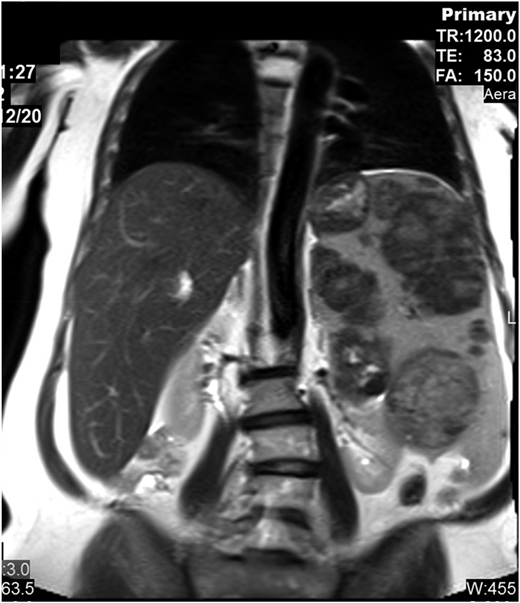

The patient presented at our Gaucher unit in 1998 at the age of 43 years and was married with 6 children. She was referred by the preoperative screening clinic (before repair of an umbilical hernia), where she was noted to have marked hepatosplenomegaly, pancytopenia, and abdominal ultrasonographic findings of multiple splenic lesions, suspicious for malignancy (Figure 2).

Abdominal magnetic resonance imaging showing hepatosplenomegaly with prominent intrasplenic lesions.

Although recognized for almost 140 years, the natural history of untreated GD has not been fully appreciated. Many mildly affected and even asymptomatic patients receive lifelong ERT because their physicians erroneously assume that, without therapy, the disease will invariably deteriorate. However, GD progression (even in those with moderate to severe phenotypes) occurs during childhood, adolescence, and early adulthood with a tendency to stabilize later in life. In the majority of the mild or asymptomatic patients, GD remains unchanged for decades.3 Our moderately affected patient has remained stable for more than 2 decades. Intrasplenic (and less commonly intrahepatic) lesions—hypoechogenic, hyperechogenic, or mixed—are typical in GD, but for the inexperienced radiologist, they may mimic hematological malignancies, as in our patient.4